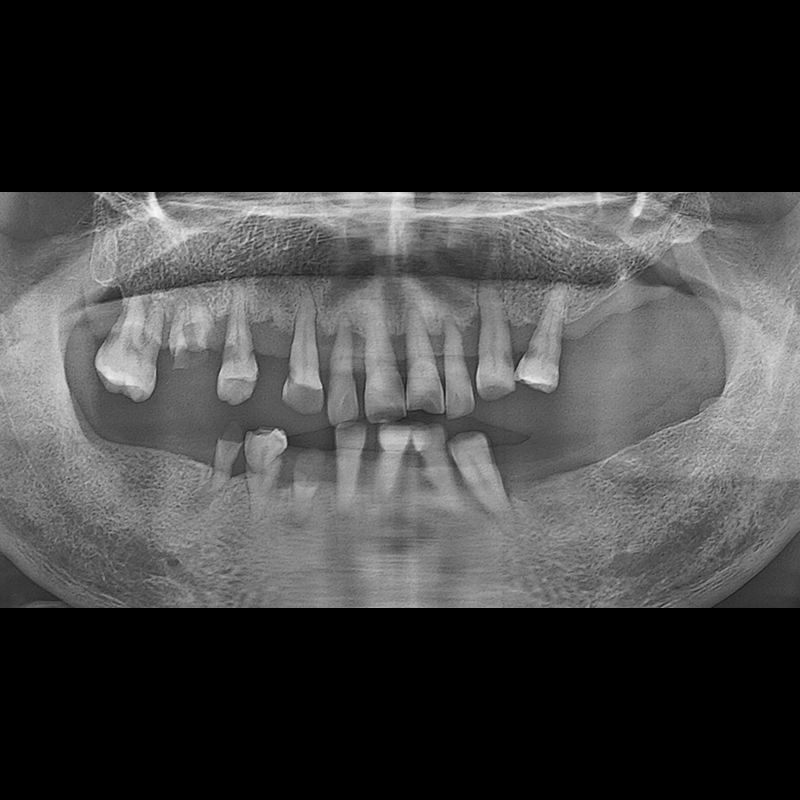

BEFORE AFTER

种植牙前后的照片 2025.05.30

在缺失的牙齿部分和难以挽救的牙齿位置植入了种植牙。